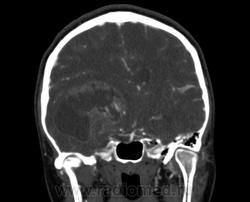

Молодая женщина, 29 лет. Обратилась на прием к неврологу 26.10.12г с  болями в шее, назначено лечение амбулаторно по сосудистой головной боли, остеохондрозу.. После 14.11.12г обратилась к другому неврологу повторно, 16.11.12г направлена в стационар. Жалобы: на снижение зрения, головные боли, головокружения, слабость, повышение температуры. Провели СКТ головного мозга натив и контрастирование. Подскажите пожалуйста, коллеги- Это опухоль? тогда какая (глиобластома, невринома, менингиома?) и локализацию. Спасибо.

Сканы с контрастированием.

Одно можно сказать точно: это не менингиома и не невринома (у тех структура однородная). Это Вам в помощь http://www.radiologyassistant.nl/en/p47f86aa182b3a/brain-tumor-systematic-approach.html

Мне кажется, что тут субэпендимарная глиома. Указываете степень дислокации, накопления и к нейрохирургам.

Согласна с Андреем Юрьевичем. Все остальное возможно, в том числе олигодендроглиома. Впрочем не принципиально. К нейрохирургам!

Только что узнала результаты вскрытия.Гистология пока не готова.

Глиобластома с прорастанием стенки правого бокового желудочка, выраженный отек, смещение срединных структур, вклинение миндалин мозжечка в БЗО.